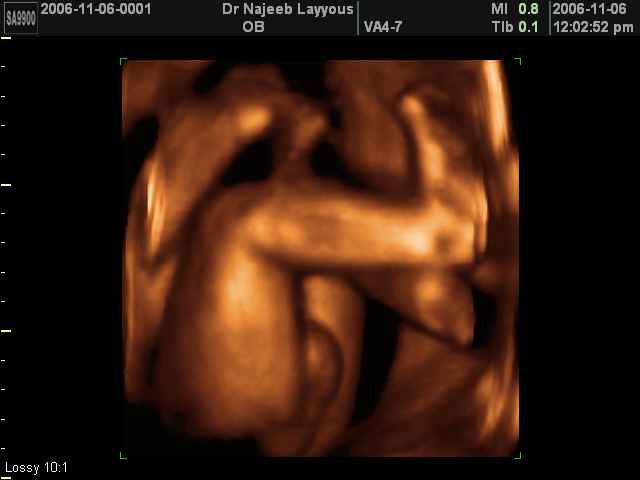

- صور لأعضاء الجنين

- صور لأطراف الجنين

صور لأعضاء الجنين بجهاز الموجات فوق صوتية ثلاثي الأبعاد | الدكتور نجيب ليوس